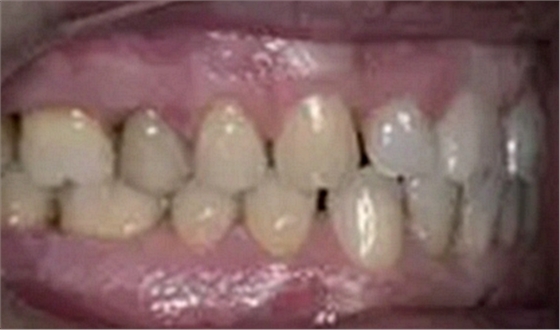

一位寻求改善微笑面容的43岁荷兰阿尔梅勒男子通过其全科牙医的介绍来到一家正畸医生的私人诊所,以纠正其错合畸形并在上颌前牙区域放置6个贴面。他属于牙形I类错合畸形,轻度骨性III类,覆合和覆盖减少以及前牙区存在间隙(图1)。

在最初的正畸咨询期间,拍摄了口内和口外照片连同一张全景片(图2),一张侧位头影片(图3)和正畸研究模型的海藻酸盐印模。